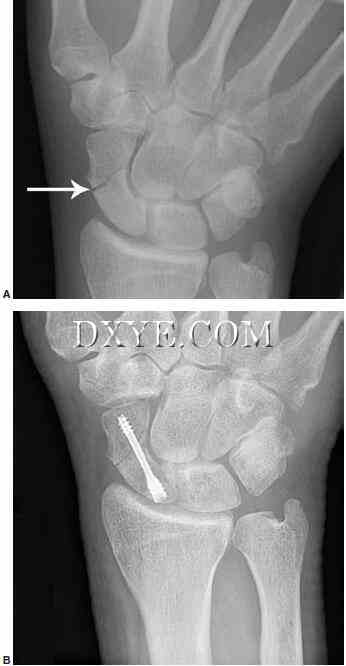

尺骨茎突骨折。 超过50%的桡骨远端骨折伴有尺骨茎突骨折,但并非所有的尺骨茎突骨折均需要修复。 手术干预取决于DRUJ的稳定性。 发现尺骨茎突基底骨折和位移大于2 mm的基底骨折会影响DRUJ的稳定性。 当根据放射照片的外观怀疑DRUJ不稳定时,对照正常的手腕检查DRUJ在中性,完全旋后和完全旋前的平移松弛。 一旦桡骨远端骨折已经修复,外科医生应该检查受伤的手腕并将其与正常侧进行比较。 如果DRUJ松弛,尤其是完全旋后,尺骨茎突修复。 可以使用克氏线,张紧带线或空心无头螺钉(图76.18)。 使用糖钳或Munster型夹板,将前臂在中性旋转下固定4至6周。

18.jpg

图 76.18.  延迟与尺骨茎突骨折不愈合DRUJ不稳定表现。A.术前X线片显示桡骨相对尺骨背侧半脱位,与尺骨茎突显示箭头移位。B.晚期术后X线片显示尺骨茎突与TFCC重新插入使用骨锚钢丝张力带。